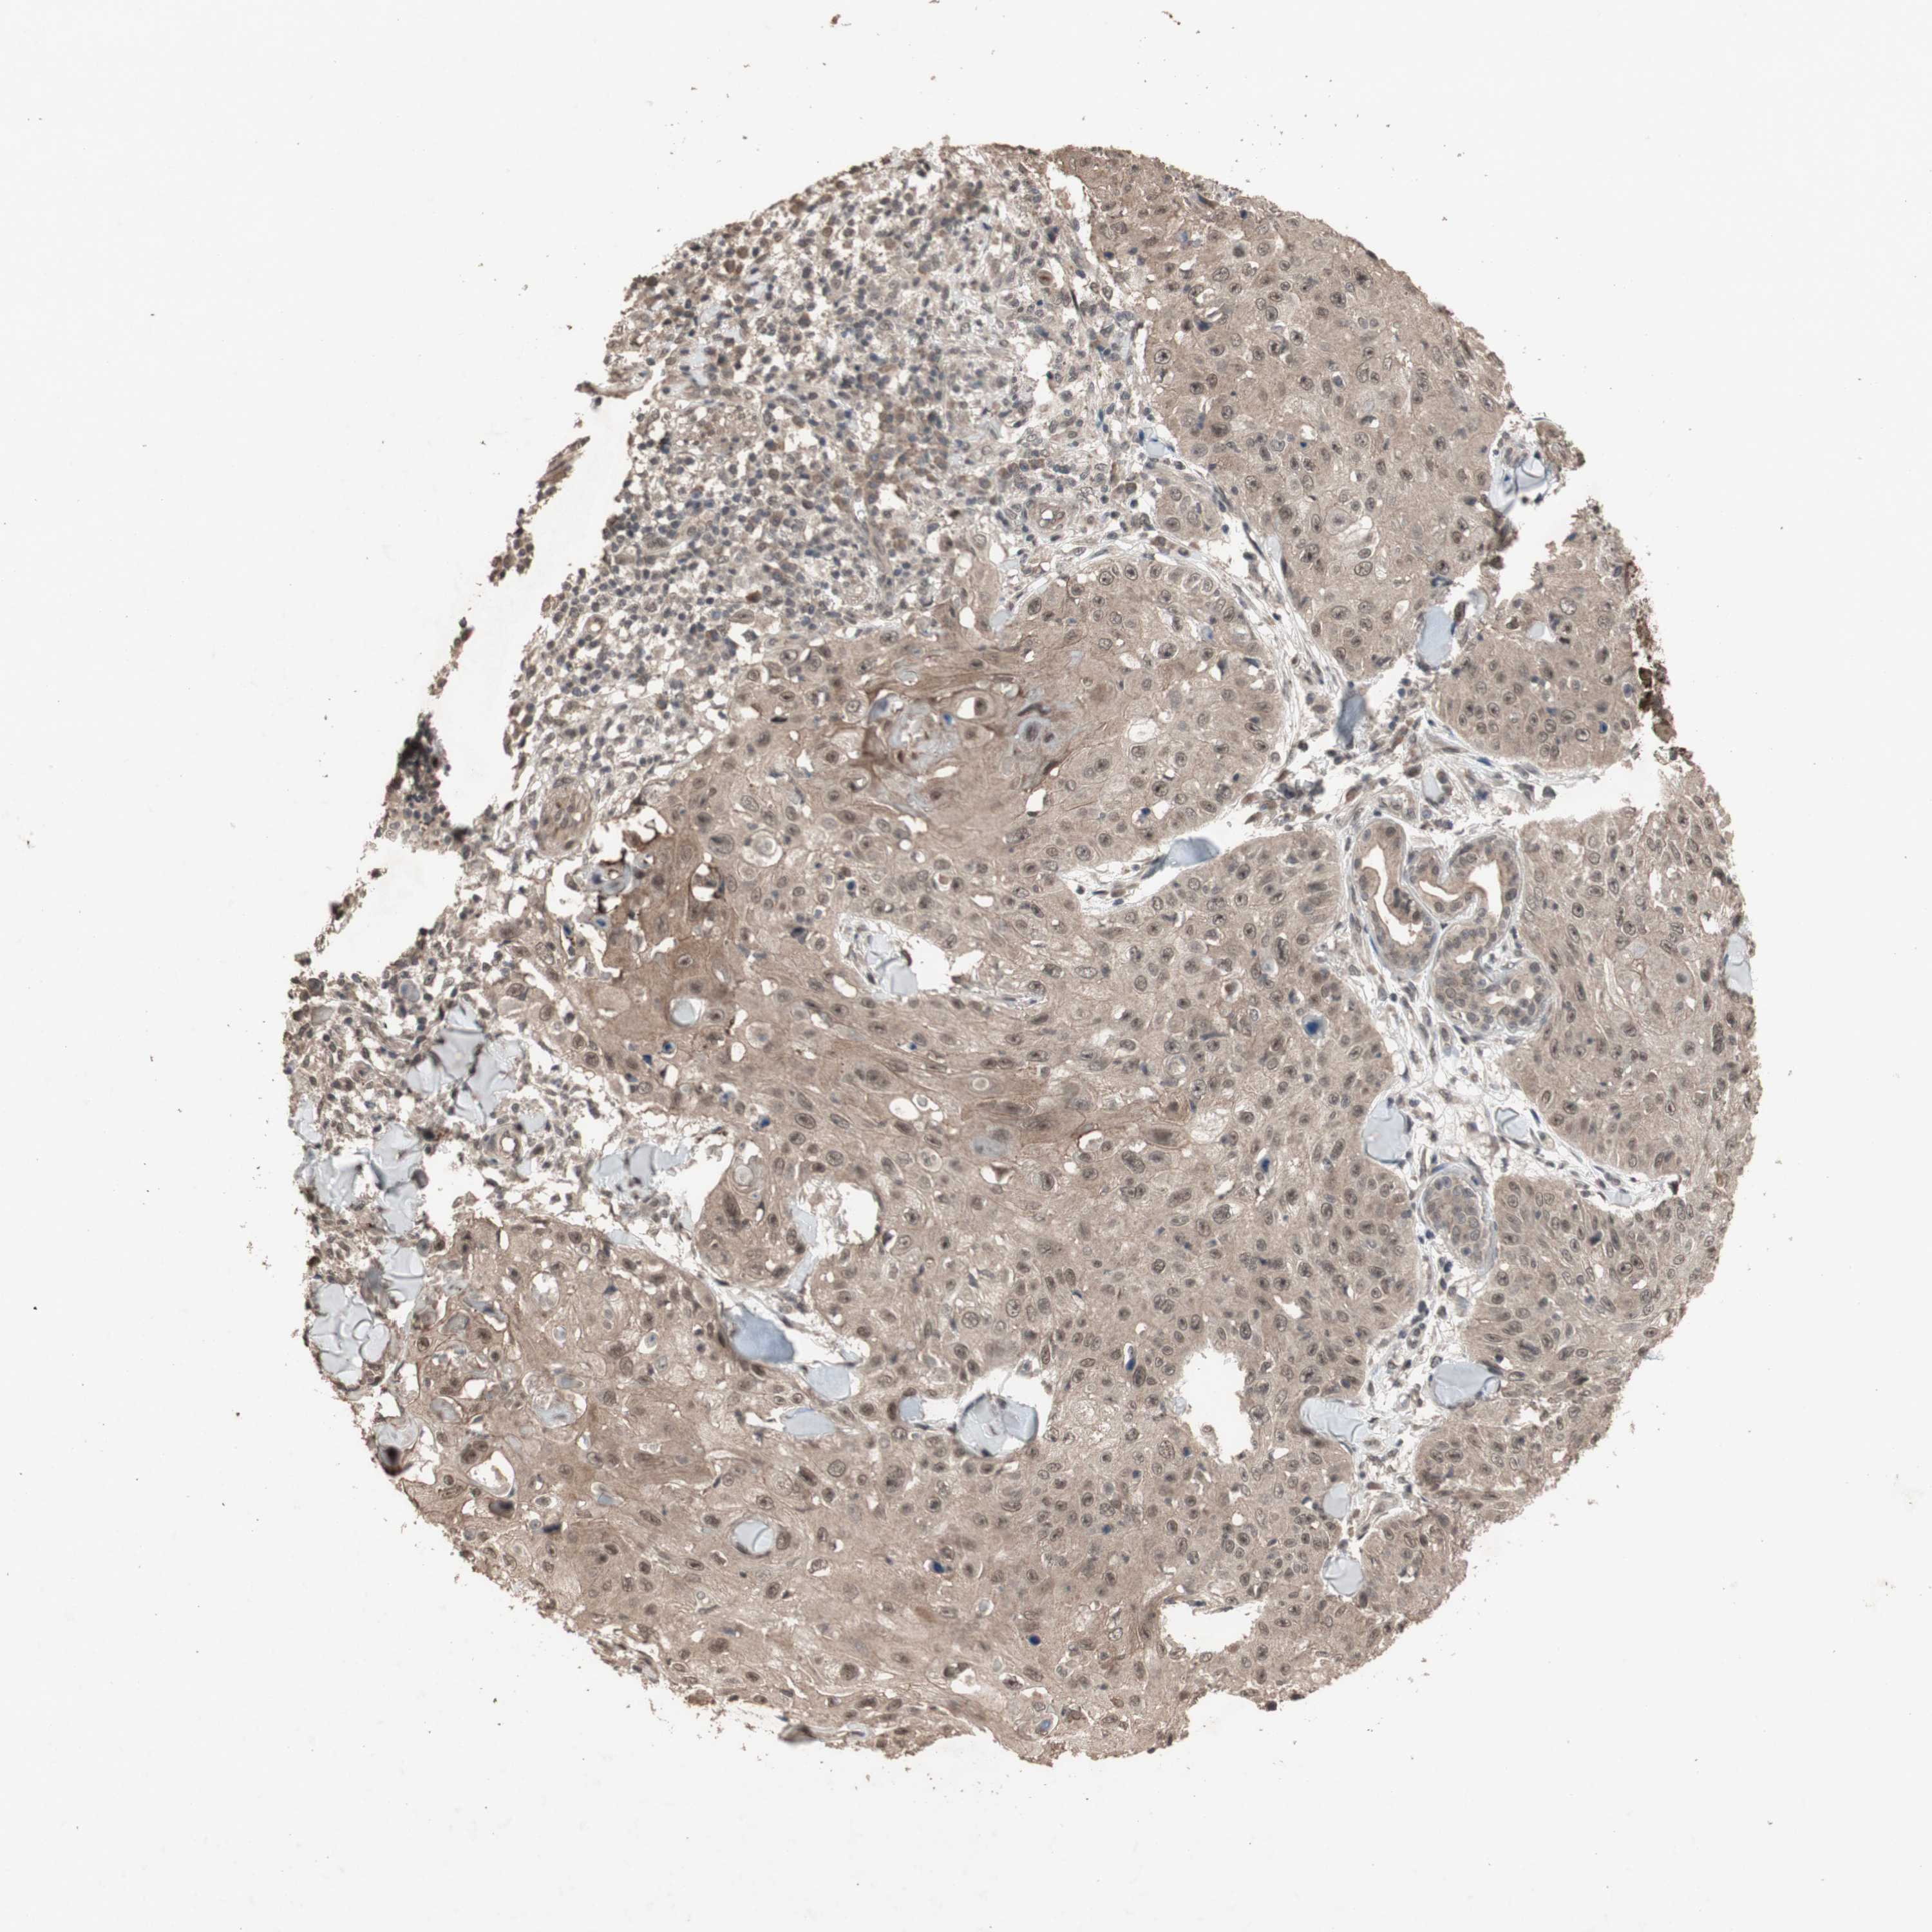

SKIN CANCER - Protein expressioni

A mouse-over function shows sample information and annotation data. Click on an image to view it in a full screen mode. Samples can be filtered based on level of antibody staining by selecting one or several of the following categories: high, medium, low and not detected. The assay and annotation is described here.

Each image is clickable and will lead to virtual microscopy that enables deeper exploration of all samples and also displays staining intensity scores, fraction scores and subcellular localization as well as patient and tissue information for each sample.

Antibody HPA006874

Antibody HPA007208

Staining

High

Medium

Low

Not detected

Intensity

Strong

Moderate

Weak

Negative

Quantity

>75%

75%-25%

<25%

None

Location

Nuclear

Cytoplasmic/membranous

Cytoplasmic/membranous,nuclear

Squamous cell carcinoma, NOS

Basal cell carcinoma